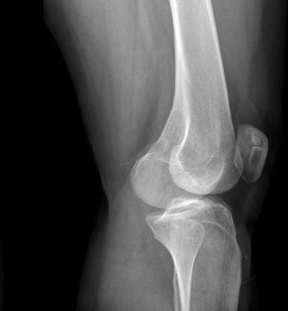

Боль в коленном суставе — один из самых частых поводов обращения к врачу-травматологу. Этот симптом может быть следствием как острой травмы, так и хронических дегенеративных изменений. Важно не откладывать обследование: колено — сложный сустав, и любое повреждение без своевременного лечения может привести к снижению подвижности или развитию артроза.

• дегенеративные заболевания — артроз, который постепенно разрушает хрящевую ткань;

Методы лечения